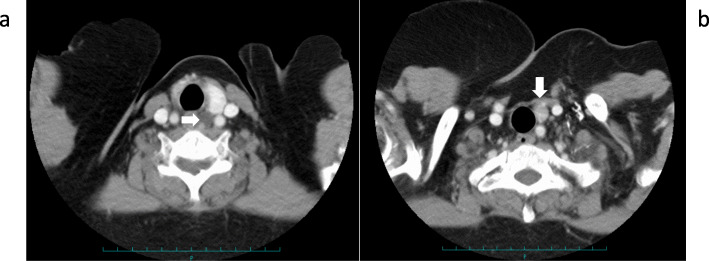

Fig. 3.

CT findings of the neck. a A mass found behind the left thyroid lobe (arrow). b A mass found caudally next to the lower pole of the left thyroid lobe (arrow)